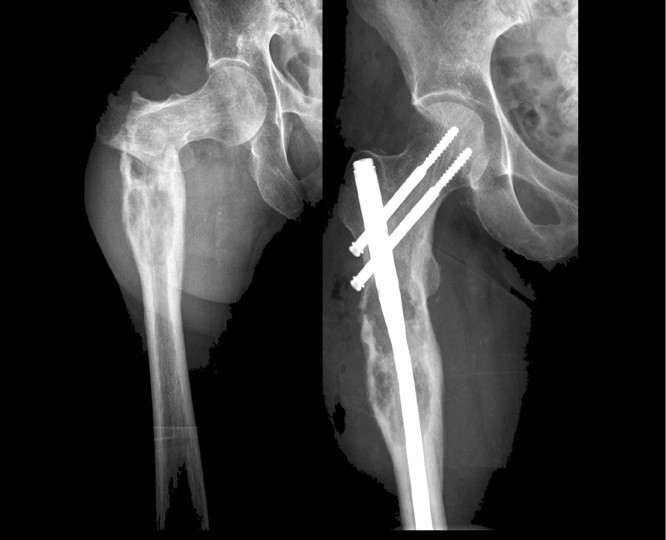

Oberschenkelhalsbruch nagel entfernen. Selten sind junge menschen im rahmen eines hochrasanztraumas betroffen. Es sollen in den nächsten wochen die schrauben entfernt werden. Wer nach erfolgreicher behandlung und gut verlaufener heilung eines oberschenkelbruchs keinerlei schmerzen oder probleme mehr hat mag sich fragen warum er die implantate überhaupt entfernen lassen soll. Das hohe risiko nach einem oberschenkelhalsbruch an einer hüftkopfnekrose zu erkranken ist mit dem einsatz der hüftgelenk endoprothese ausgeschlossen.

Da bei mir eben nach einem jahr der zeitpunkt beruflich ganz schlecht war wollte ich ihn nach 1 3 4jahren entfernen lassen. Der gammanagel und die dynamische hüftschraube sind zwei implantate die verwendet werden um hüftgelenksnahe brüche des oberschenkelknochens zu stabilisieren. Werden mit einem sogenannten gamma nagel versorgt. Schließlich muss sich der patient dazu einem zweiten eingriff unterziehen.

Marknagelung Wikipedia